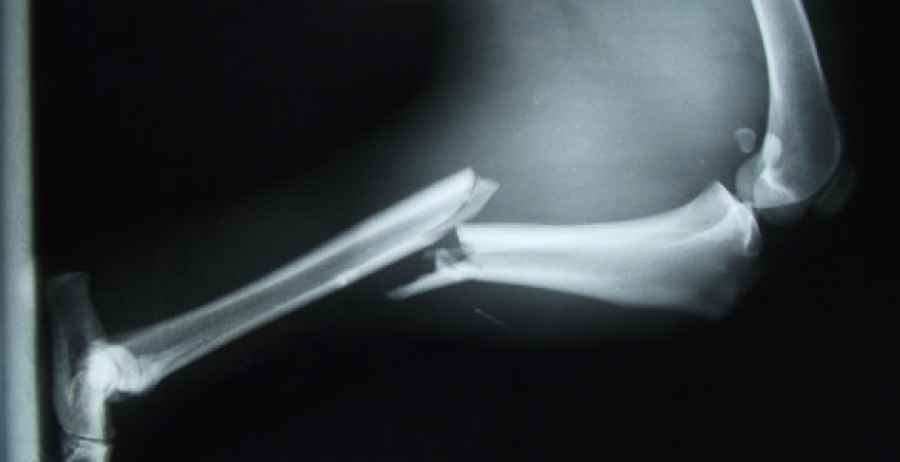

Se estima que, cumplidos los 50 años, hasta una de cada tres mujeres y uno de cada cinco varones acabarán padeciendo una fractura por culpa de la osteoporosis. Sin embargo, y a tenor de las nuevas evidencias, parece que la toma de suplementos con calcio y/o vitamina D no ayuda a evitar que esto pase.